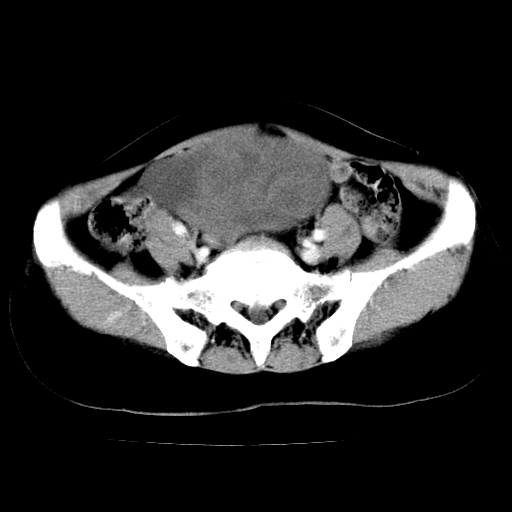

标题: CT24785:女,62岁,发现下腹部肿物半年。 [打印本页]

女,62岁,发现下腹部肿物半年,下腹部不适。

老年女性患者,盆腔囊实性占位,ct增强不均匀强化,未见壁结节,未见腹水及盆腔积液,考虑附件囊腺瘤可能性大!